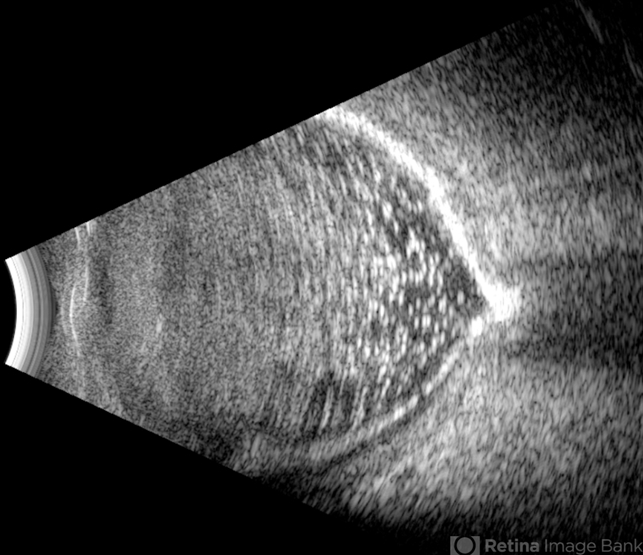

- calcification, Retina detachment, vitrectomy

- Ultrasonography device

- B-mode ultrasound of a vitrectomized eye reveals emulsified silicone oil in the vitreous cavity, retinal detachment, and calcification of the retina and optic nerve head.